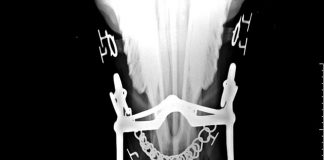

Robert Cook, FRCVS., PhD., Professor of Surgery Emeritus of Tufts University,...

Berlin, Germany (Weltexpress). Robert Cook is a US horses researcher and was founder of the Veterinary School at Tufts University Massachusetts, a 1952 graduate...